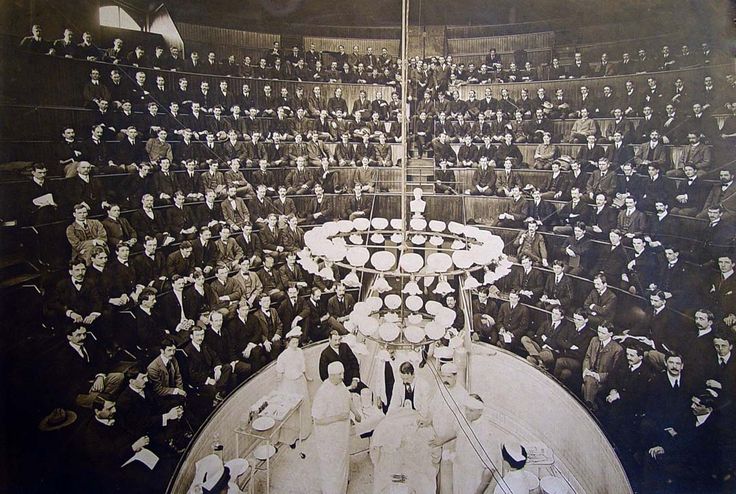

Upon a patient’s arrival, multiple people are poking, prodding, screaming, shouting, slicing, sticking, cutting, and tearing… at the life and limb of this latest entrant to the trauma bay.

But the surgeons, they prefer the deafening silence of the patient because the stakes are raised, the opportunity to transport them to the surgical theater more likely, and their god-like skills are soon to be exercised.

In a nutshell, that is the humanity that is absent from the trauma bay. It is a rarity for someone to ask for a patient’s name; no one states a desire to care for you; no one even thinks of doing either of those until the patient is either on the way to the CT scanner, surgical theater, or morgue.